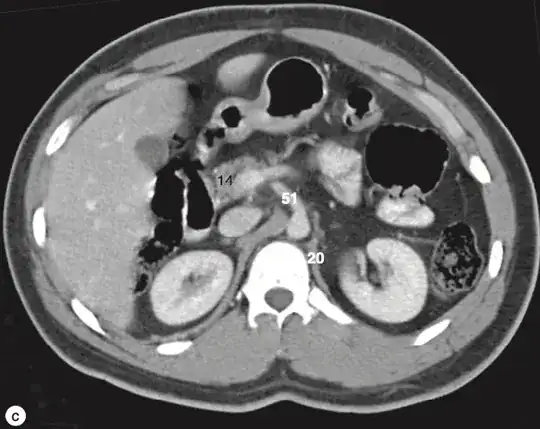

How do we differentiate the the truncus coeliacus from the superior mesenteric artery when looked at from an MRI in the axial plane? For example, the images that I attached, how can I differentiate 8 from 51? I cannot see a difference. (Source of images: Imaging atlas of human anatomy, Weir & Abrahams')

Looking at this diagram, the coeliac trunk itself bifurcates shortly after branching from the aorta. The SMA moves inferiorly and anteriorly in a more straight path. This would make 51 the SMA and 8 the coeliac trunk. This would fit with the liver appearing smaller at the more inferior level of the SMA.

Actually I’m going to make an edit. Disclaimer - I’m not sure how accurate this is, but it seems coeliac trunk moves to the right shortly after branching from the aorta. The SMA moves inferiority and anteriorly in a more straight path. This would make 51 the SMA and 8 the coeliac trunk. This would fit with the liver appearigg by smaller at the more inferior level of the SMA. – Chris Dec 01 '23 at 20:46